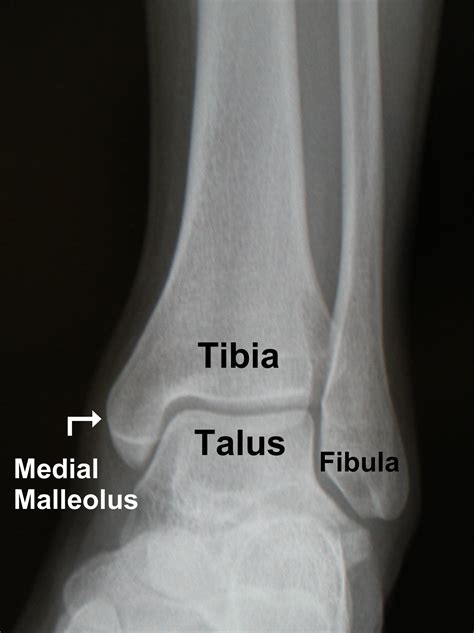

A hairline fracture, also known as a stress fracture, is a thin crack in the bone. In the case of a hairline fracture ankle, this crack typically occurs in one of the three bones that form the ankle joint: the tibia, fibula, or talus. These fractures are often caused by repetitive stress or a sudden impact, such as twisting the ankle or landing awkwardly after a jump.

Diagnosing a hairline fracture ankle involves a combination of physical examination and imaging tests. Your healthcare provider will likely perform the following steps:

• Physical Examination: The doctor will assess the affected area for swelling, tenderness, and range of motion.

• Imaging Tests: X-rays are the most common imaging test used to diagnose fractures. However, hairline fractures may not always be visible on initial X-rays. In such cases, additional imaging tests such as MRI or CT scans may be required.